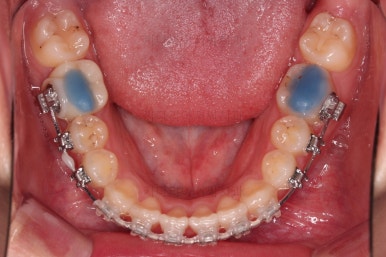

처음 장치를 부착한 모습인데요.

이번 환자분이 부산옥니교정에 사용한 장치는 엠파워 클리어라고 하는 자가결찰 세라믹 장치였습니다.

철사를 잡아주는 캡(결찰)이 브라켓에 달려있어 스스로 묶고 풀고가 가능한(자가) 세라믹 재질의 장치라는 뜻인데요.

대표적으로는 엠파워 클리어, 클리피씨 등이 있습니다.

가벼운 철사에서 두꺼운 철사로 주기적으로 바꿔감에 따라 치열이 점점 가지런해지고 있습니다.

현재 모습도 나쁘지 않지만 좀 더 디테일을 맞춰주기 위해서 고무줄도 끼고, 왜소치 때문에 생기는 사이즈 부조화문제로 정중선이 안맞는 점은 일정 부분 수용하면서도 최대한 맞춰보기로 했습니다.